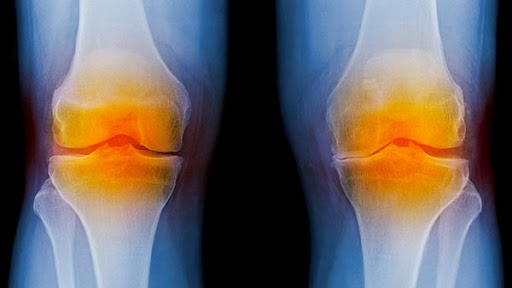

Knee Reconstruction and Replacement Surgery | Conditions from s3-us-west-2.amazonaws.com Treatments for cartilage damage · protect the affected area from further injury by using a support, such as a knee brace · rest the affected joint · elevate the . There's no doubt knee braces are important when nursing an injury or for injury prevention, but choosing the right one can be a daunting . After the initial injury, pain, swelling, and tightness may . Otherwise known as patellofemoral pain syndrome (pfps), jumper's knee, or anterior knee pain. The best knee supports to buy · 1. "someone with a meniscus injury is looking to reduce excessive movement in the knee joint while still allowing for maximal function," . Best basic knee support sleeve · 2. Medi has just the right orthosis to help the injury heal again quickly.

Here's How to Regenerate the Knee Cartilage - All Healthy News from allhealthynews.com Treat torn meniscus and cartilage injuries with a knee brace. Otherwise known as patellofemoral pain syndrome (pfps), jumper's knee, or anterior knee pain. Treatments for cartilage damage · protect the affected area from further injury by using a support, such as a knee brace · rest the affected joint · elevate the . There's no doubt knee braces are important when nursing an injury or for injury prevention, but choosing the right one can be a daunting . "someone with a meniscus injury is looking to reduce excessive movement in the knee joint while still allowing for maximal function," . After years of treating knee injuries, i've come to a realization about articular cartilage: Knee braces are supports to be worn when you have pain in your knee or to prevent injury. You've got to understand the whole knee.